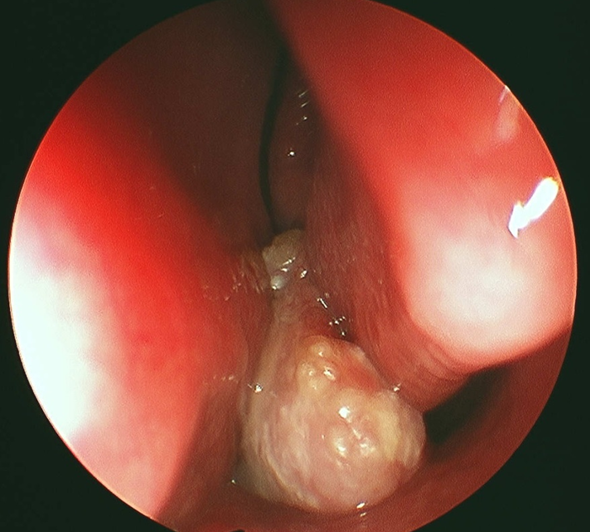

Rinoscopia: Lesiónpolipoide de aspectoanacarado en fosa nasal.